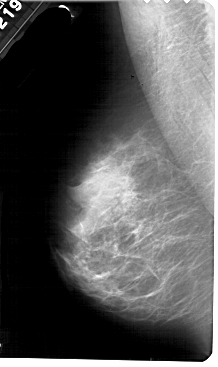

A_1614_1.RIGHT_MLO

RIGHT_MLO LINES 5491 PIXELS_PER_LINE 3151 BITS_PER_PIXEL 12 RESOLUTION 43.5 OVERLAY

FILE: A_1614_1.RIGHT_MLO.OVERLAY

TOTAL_ABNORMALITIES 1

ABNORMALITY 1

LESION_TYPE CALCIFICATION TYPE PLEOMORPHIC DISTRIBUTION CLUSTERED

ASSESSMENT 4

SUBTLETY 1

PATHOLOGY MALIGNANT

TOTAL_OUTLINES 1

BOUNDARY